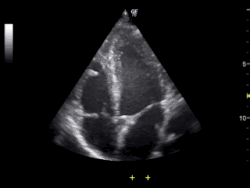

Ultrasonografia

Ultrasonografia (USG) wykorzystuje ultradźwięki do tworzenia wizualizacji badanego organizmu. Korzysta ona ze zjawiska odbicia i rozpraszania się fali dźwiękowej na granicy ośrodków. Wykorzystuje zjawiska rozchodzenia się, rozpraszania i odbijania fal ultradźwiękowych na granicy ośrodków. Stosowana jest przede wszystkim do określania rozmiarów, lokalizacji i głębokości usytuowania względem powierzchni ciała badanych narządów. Jedynym jej ograniczeniem jest stosowanie jej tylko do tkanek miękkich złożonych w dużej mierze z wody, dobrego przewodnika fal ultradźwiękowych.

Jedna z popularniejszych metod obrazowania stosowana od lat 60. XX wieku. Jest to jedna z tańszych i częściej stosowanych metod obrazowania. Swoją popularność osiągnęła dzięki ogólnej dostępności i niewielkiemu kosztowi przeprowadzenia. Z powodu nieinwazyjności i braku skutków ubocznych tej techniki, jest ona stosowana podczas badań prenatalnych. Pierwszym klinicznym zastosowaniem USG była diagnostyką płodu. Kolejną ważną zaletą tej metody jest to, że pozwala ona na otrzymywanie wizualizacji w czasie rzeczywistym. Możliwość obserwacji w czasie rzeczywistym oraz natychmiastowa możliwość diagnozowania również znacząco wpłynęły na popularność tej metody obrazowania.

Obecnie istnieje wiele zastosowań i odmian badania ultrasonograficznego, m.in. możliwość przedstawienia wyniku badania USG w trójwymiarze poprzez połączenie kilku sekwencji obrazów. Jednym z zastosowań USG jest USG dopplerowskie.